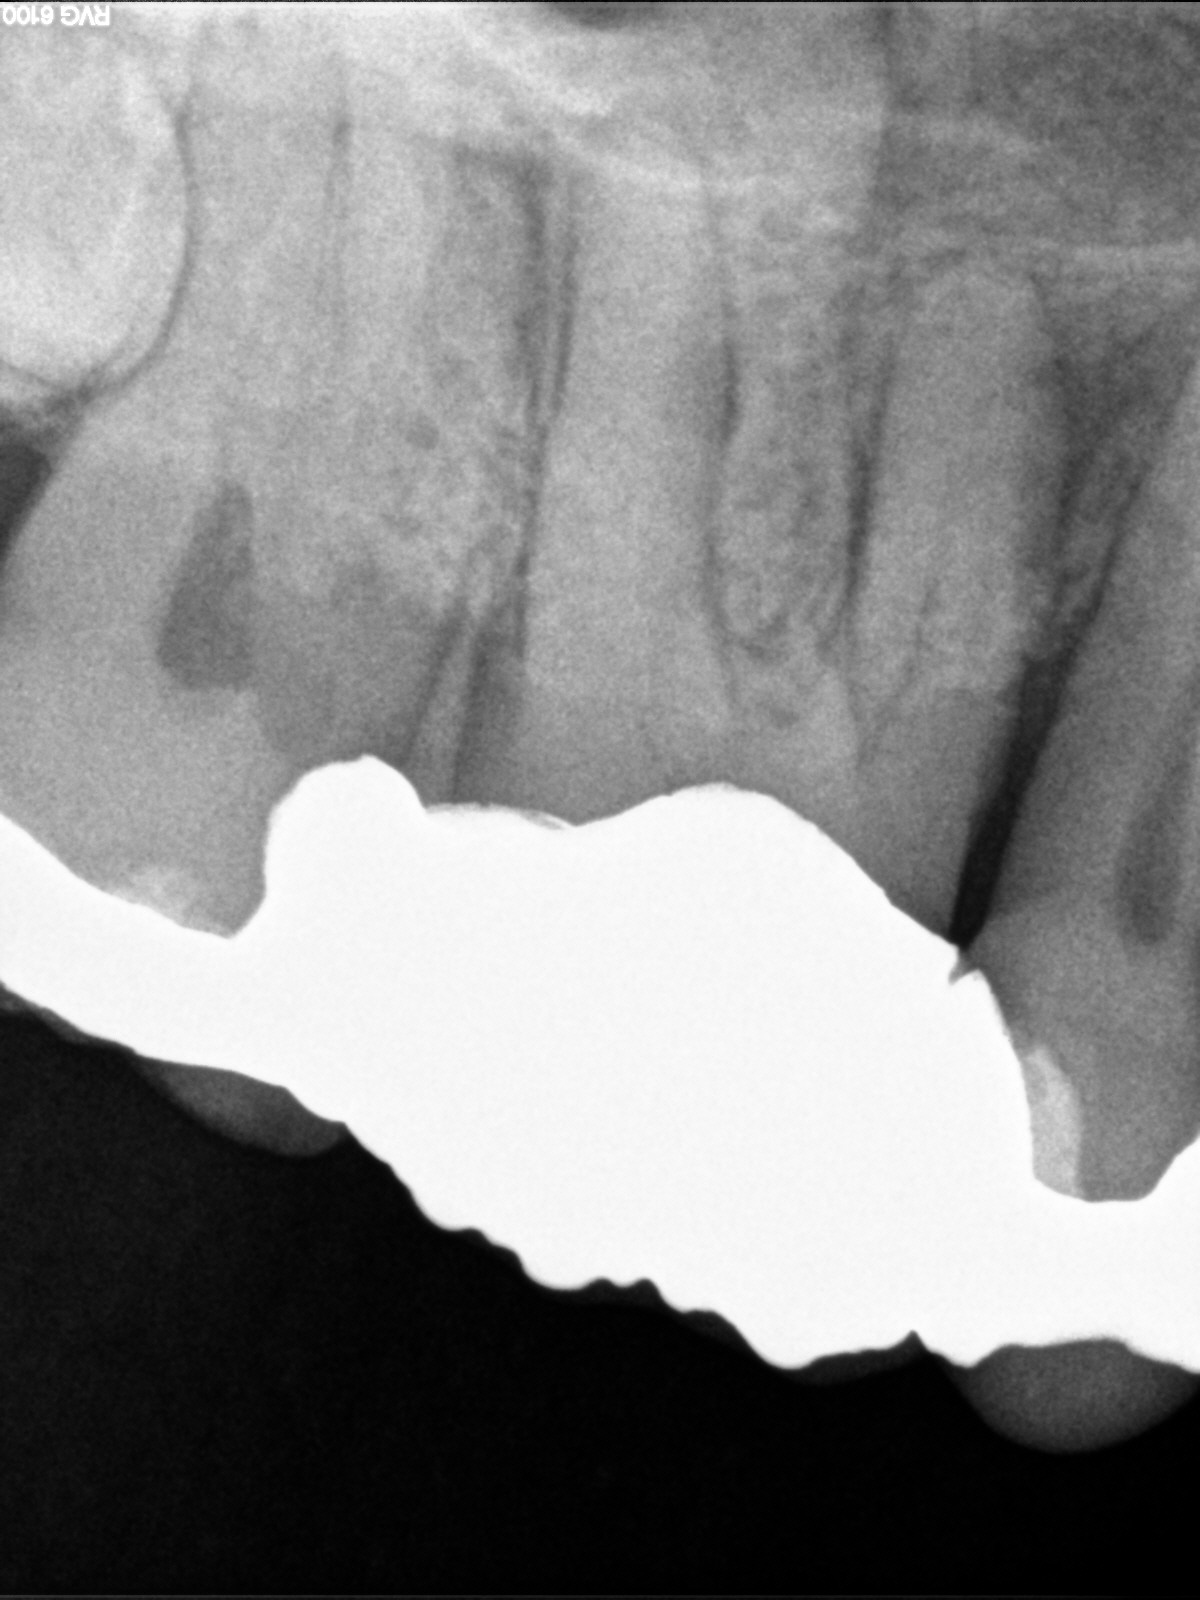

Immer schön skeptisch bleiben 4